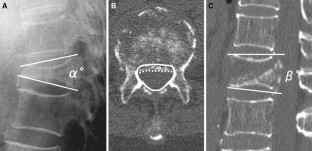

Percutaneous vertebroplasty was prospectively performed for 244 patients with OVCF with IVC; 30 had DND and 214 did not. Radiographic parameters of local kyphotic angle, percent spinal canal compromise and intravertebral instability were investigated for correlations to DND. Procedural outcomes were evaluated using visual analog scale (VAS), Oswestry Disability Index (ODI), and modified Frankel grades.

Before vertebroplasty, no substantial difference in local kyphotic angle was seen between OVCF with IVC with and without DND, but percent spinal canal compromise and intravertebral instability were greater in OVCF with IVC with DND (P < 0.001). After vertebroplasty, 25 of 30 cases (84 %) of OVCF with IVC with DND achieved clinically meaningful improvement (CMI), but 5 (17 %) did not. Patients with CMI showed substantial improvements in intravertebral instability (P < 0.001), and no change in local kyphotic angle or percent spinal canal compromise. In five patients without CMI, four showed an initial improvement, but subsequent vertebral fracture adjacent to the treated vertebra caused neurologic re-deterioration. One patient with percent spinal canal compromise 54.9 % and intravertebral instability 4° achieved no neurologic improvement following vertebroplasty. No serious complications or adverse events related to the procedure were encountered.

Intravertebral instability is the dominant cause of DND. Percutaneous vertebroplasty appears effective and safe in the treatment of OVCF with IVC with DND. Patients with less intravertebral instability and severe spinal canal compromise could be candidates for conventional surgical treatment.